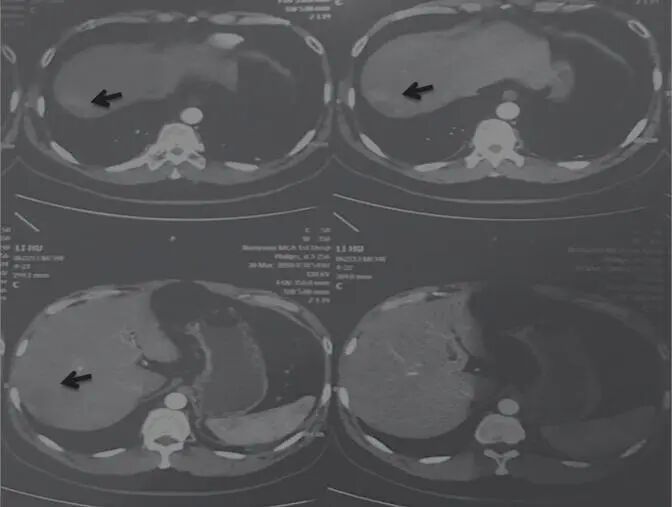

2017年11月18日,患者自述喝酒、熬夜,导致转氨酶轻度升高。嘱患者仍用原方服用3月余。2018年3月30日,检查示肝占位病变,考虑肝癌。肿瘤大小为53.4mm×41.8mm(图3)。

图3 舒达少阳防治肿瘤验案2018年3月30日CT结果

治疗回顾:男性,32岁,乙肝病史10年,2016年5月7日,检查示肝右叶巨大占位性病变,15cm×13.2cm;经用舒少阳、散结聚、健脾胃、宁心神的方法治疗,2018年3月30日复查示肝顶部积水,肝右后叶可见不规则肿块,边缘模糊,最大5.34cm×4.18cm,纯中药治疗后肿块体积减小,带瘤生存,生活质量好。